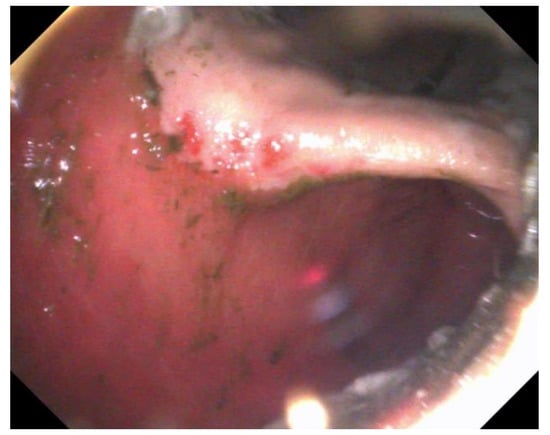

The use of histopathology to assess disease, especially of the glandular mucosa, is becoming increasingly described [67,88,119,120]. One study directly comparing gross EGGD to histopathological disease showed poor correlation, with 71% of grossly normal stomachs having mild gastritis, and all EGGD lesions demonstrating various degrees of gastritis histologically, regardless of gross severity [88]. Another study demonstrated both glandular gastric lymphoplasmacytic inflammation and eosinophilic infiltrate in a relatively small sample population [67]. The comparison of biopsy techniques feasible via endoscopy to full thickness samples post-mortem found the ‘double bite’ technique to yield the best samples for assessment [88]. Larger samples for histopathology are described using a snare when lesions are sufficiently raised, such as glandular polyps (Figure 1) [121].

Figure 1.

An adenomatous polyp in the pyloric region.